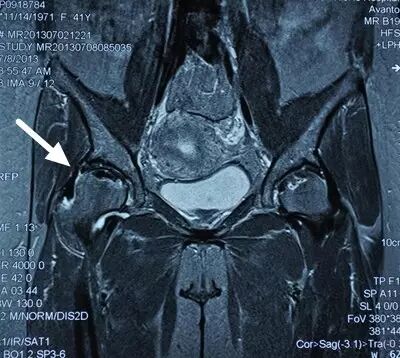

I期病人有髋部症状,X线片正常,磁共振出现异常

I期的患者在口服以上药物的同时,可以行股骨头坏死钻孔减压术,并且要定期复查,密切观察病情发展,尽量避免重体力劳动和爬山爬楼。